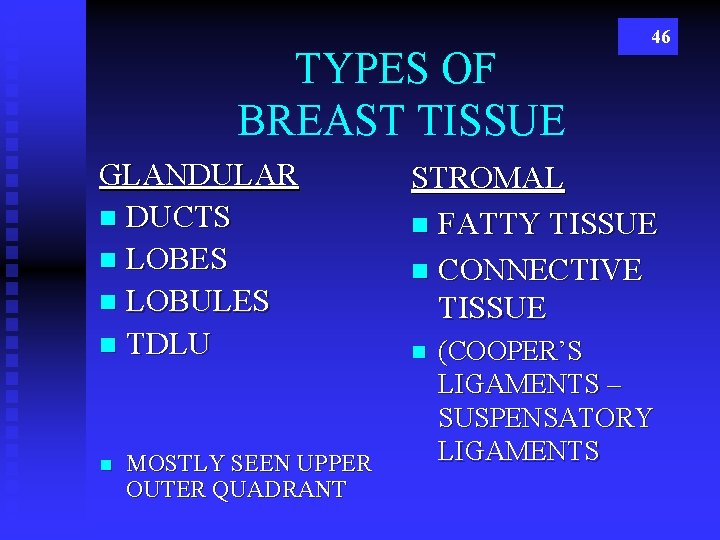

TYPES OF BREAST TISSUE GLANDULAR n DUCTS n LOBES n LOBULES n TDLU n MOSTLY SEEN UPPER OUTER QUADRANT 46 STROMAL n FATTY TISSUE n CONNECTIVE TISSUE n (COOPER’S LIGAMENTS – SUSPENSATORY LIGAMENTS